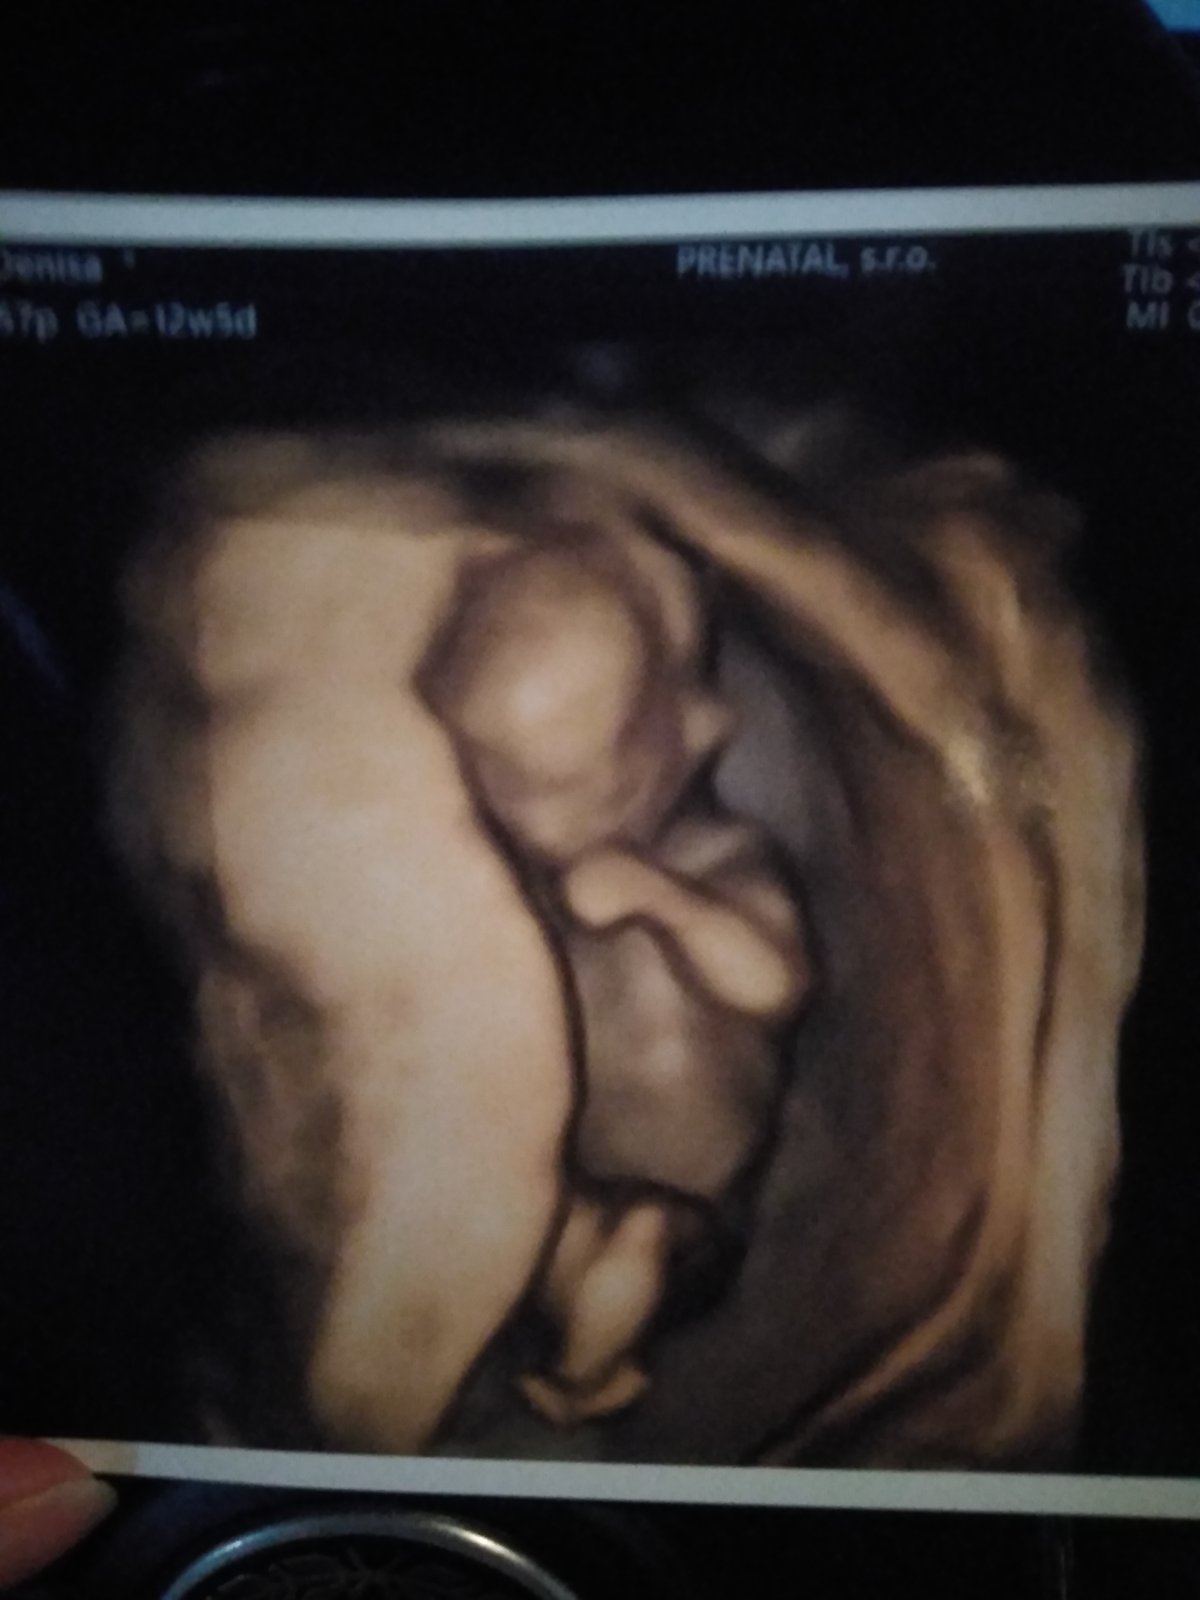

@helenky11 bolo to nase tretie umele. Prve dve som pnkovala a nevysli. Teraz chodim normalne do prace a mala som tu sesterku z anglicka chodili sme po turach po nakupoch proste uplne som vypla a nemyslela na to. Mala som kratky protokol s menopurom. 13dni pychania a hned vyber lebo boli velke alebo male. Dali sme si vsetky mozne doplnky. Lepidlo aj partnerovy vybrali naj spermie. Teraz neviem presne ako sa to vola myslim ze MACS a embrioglue. Uplne sa trasiem nemozem tomu uverit ze to vyslo. Vcera mal partner narodky robila som si test a nic. Tak som uz bola v tom ze nic z toho zas. Zajtra este pojdem na krv a modlit sa az to dopadne cele dobre😘